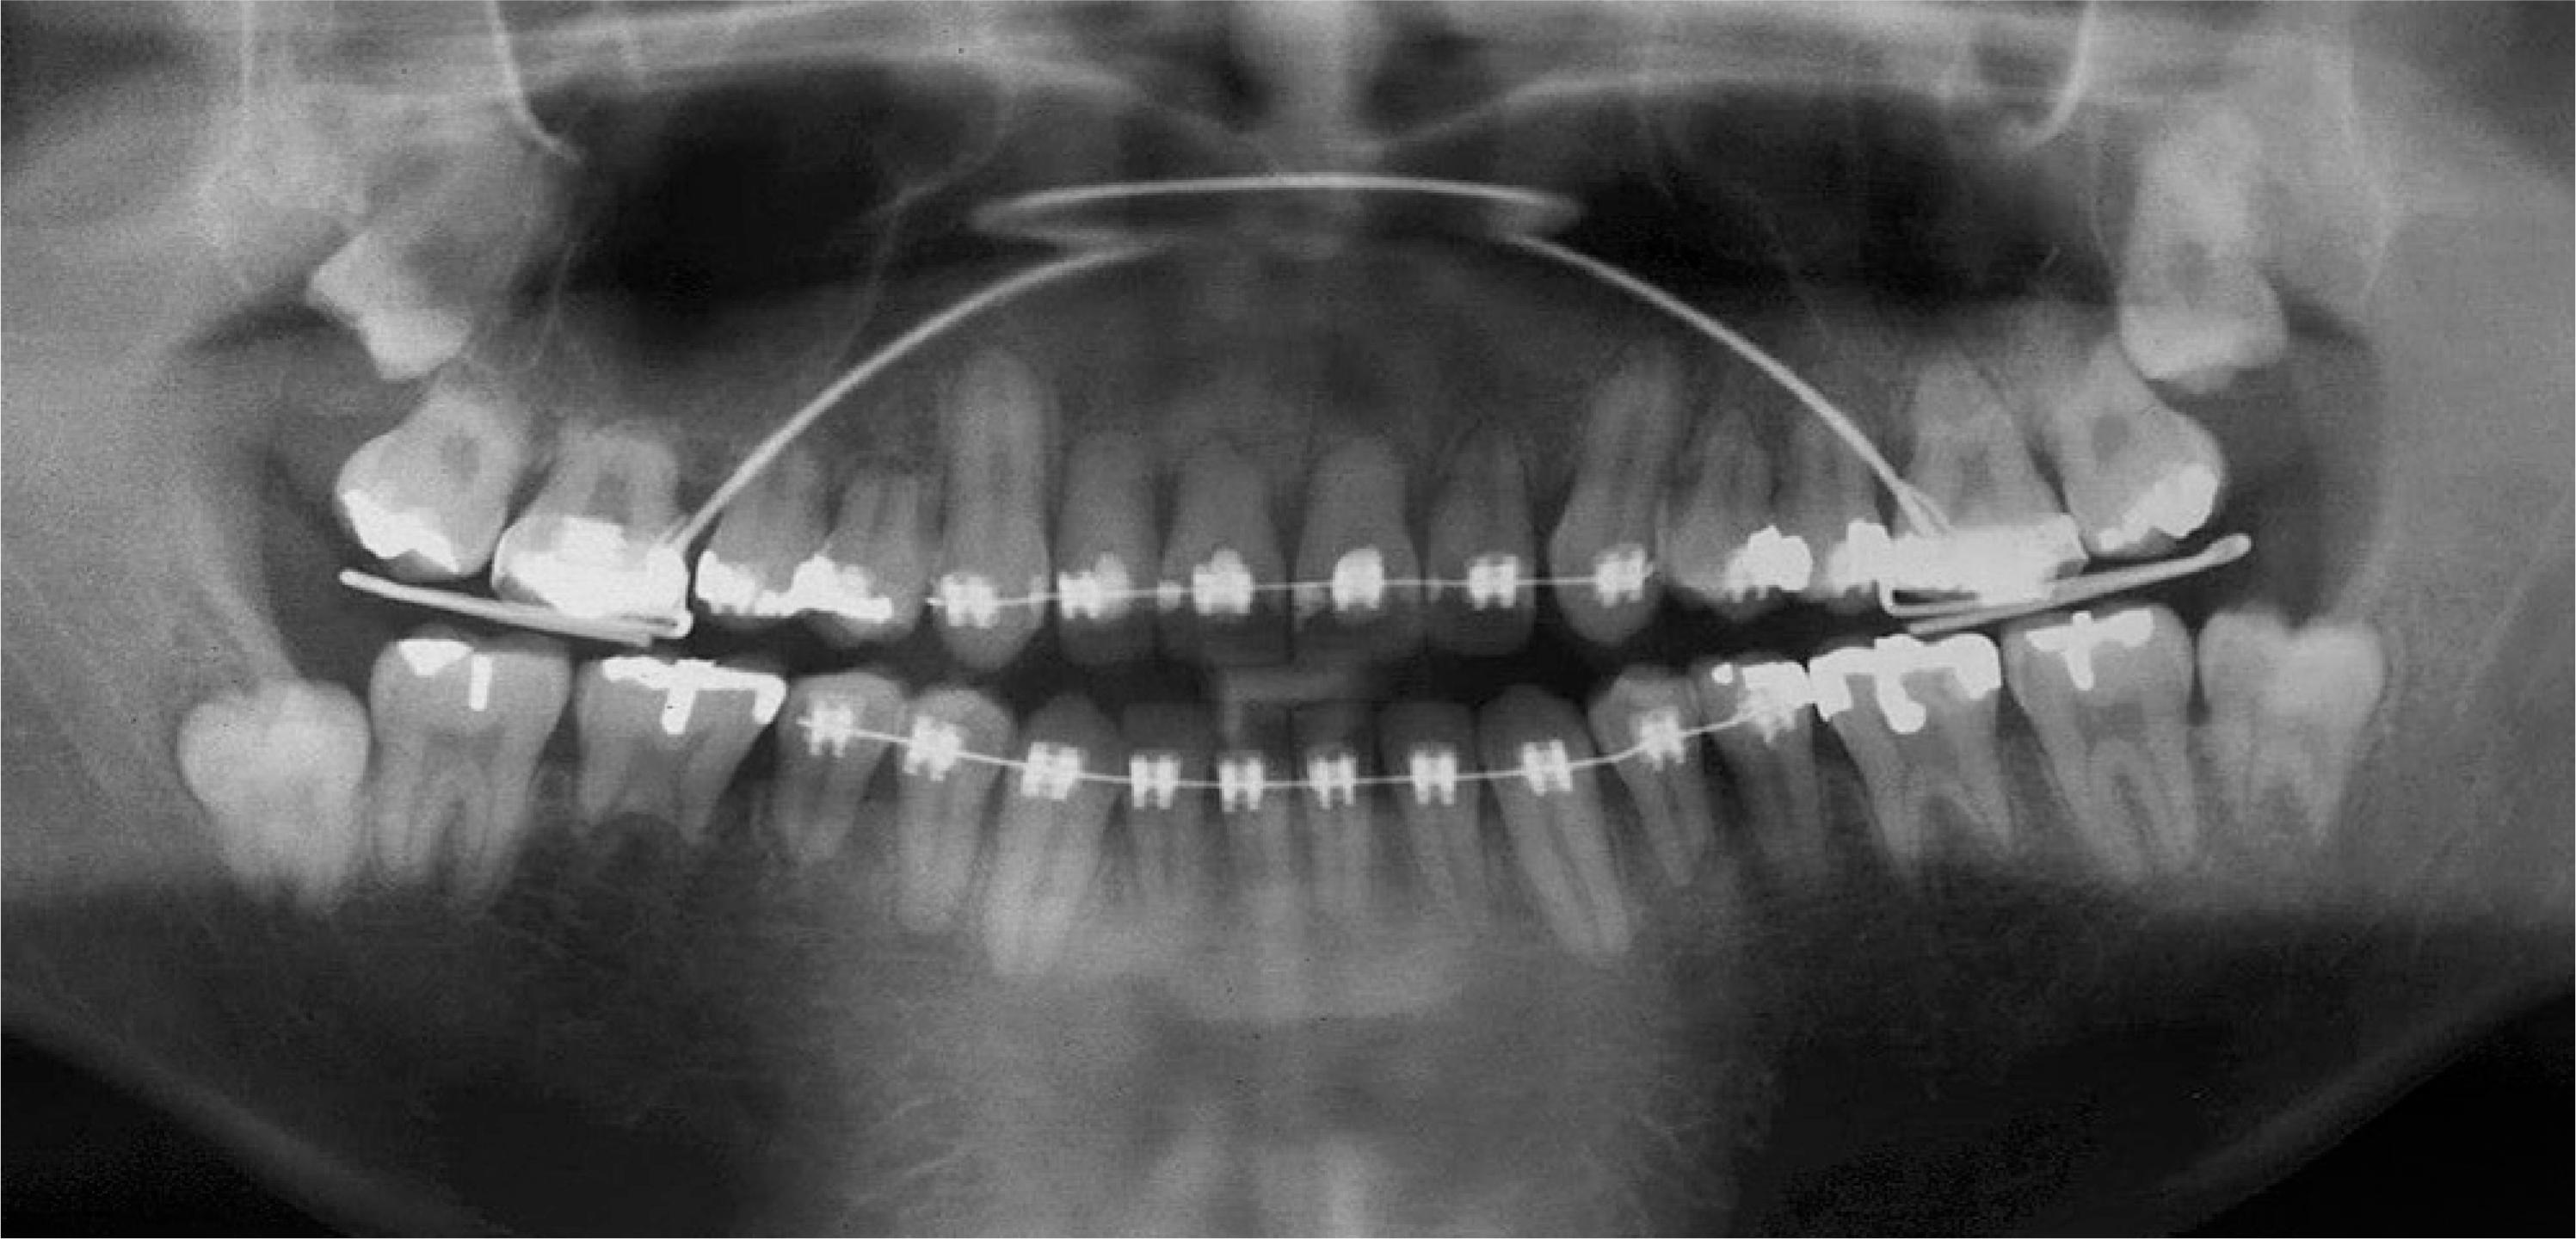

Bác sĩ cần chụp phim X-quang định kỳ (6 - 12 tháng/lần) để so sánh chiều dài chân răng. Nếu phát hiện tiêu răng sớm, giải pháp duy nhất là tạm dừng lực từ 2 - 3 tháng để mô chân răng có thời gian tự phục hồi lớp xi măng bảo vệ.